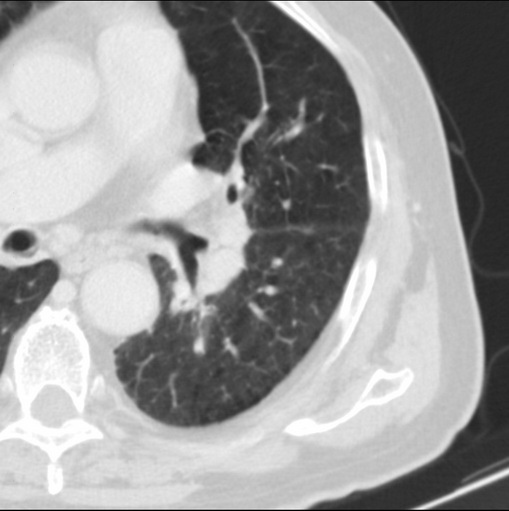

男性患者 81岁 咳嗽 咳痰 咯血

左肺中心型肺癌并:1.左肺阻塞性肺炎;2.纵隔淋巴结肿大;

考虑左上肺癌并阻塞性肺炎,左肺转移、左肺门及纵隔淋巴结转移。

肿块贴近左肺门,包绕左上肺动脉,形态不规则。肿块增强扫描中度强化。纵膈内主动脉弓左旁间隙、气管隆突前、下间隙见多枚淋巴结影。综上考虑左侧中央型肺癌可能性大。图片没有完整上传,尤其是左肺上叶支气管分支层面没有上传,因此不好判断是叶支气管中断还是段支气管中断。另外,下图红色部分所示是“黏液支气管征”吗?